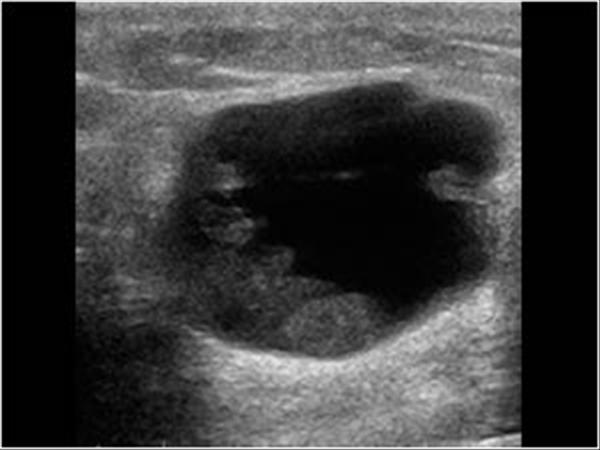

Ung thư vú

» Thông tin: Nữ giới – 82 tuổi.

» Lâm sàng: Khối tuyến vú.